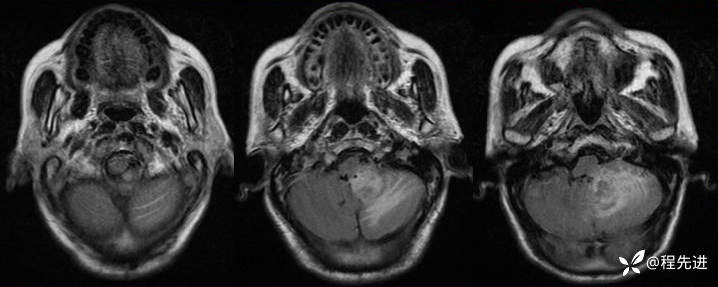

DWI:

img